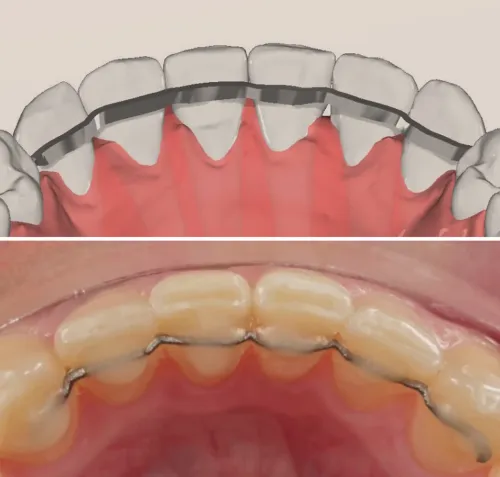

Descrizione

Dispositivo di contenzione post-trattamento progettato per mantenere i risultati ottenuti. Garantisce stabilità a lungo termine.

Caratteristiche Tecniche

- Design progettato in 3D

- Materiale in Beta Titanio Biomedicale

- Minimo spessore e massimo comfort

Indicazioni

- Fine di ogni trattamento ortodontico

- Mantenimento posizione denti

- Prevenzione delle recidive

- Utilizzabile in pazienti con problemi di parodonto per la stabilizzazione dentale

- Utilizzo a lungo termine

Vantaggi

- Elasticità: riduzione stacchi

- Materiale anallergico (Nichel-free)

- Semplicità template per l'applicazione

- Mantiene risultati nel tempo

- Discreto ed estetico

- Confortevole

- Lunga durata

- Facilità di gestione

Tempi di Trattamento

Utilizzo: permanente (fisso) | Controlli: ogni 6-12 mesi | Consigliata igiene orale periodica